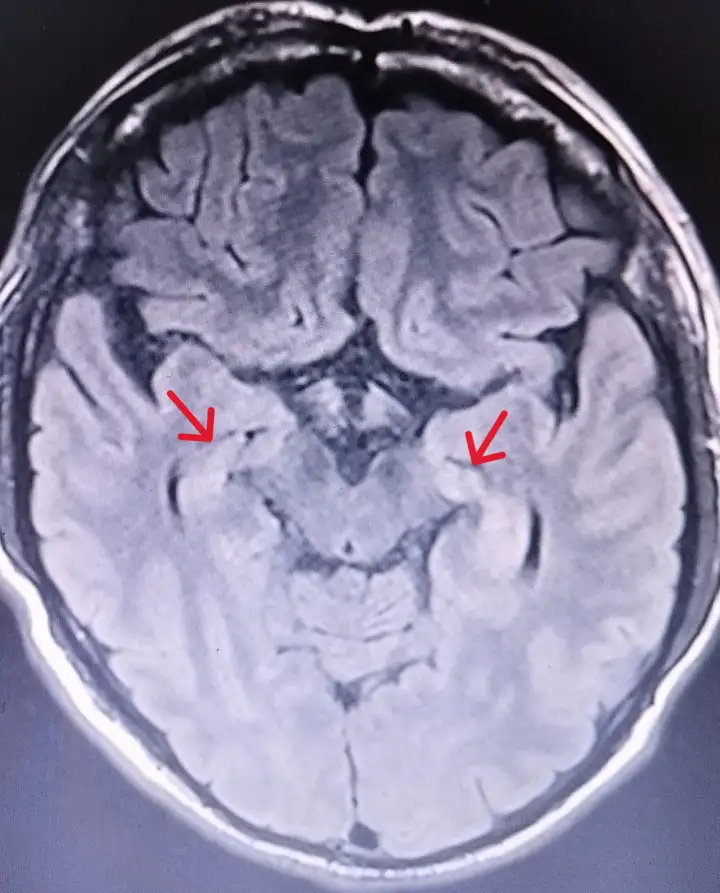

外院MR检查图像:

MR提示:左侧海马异常信号。